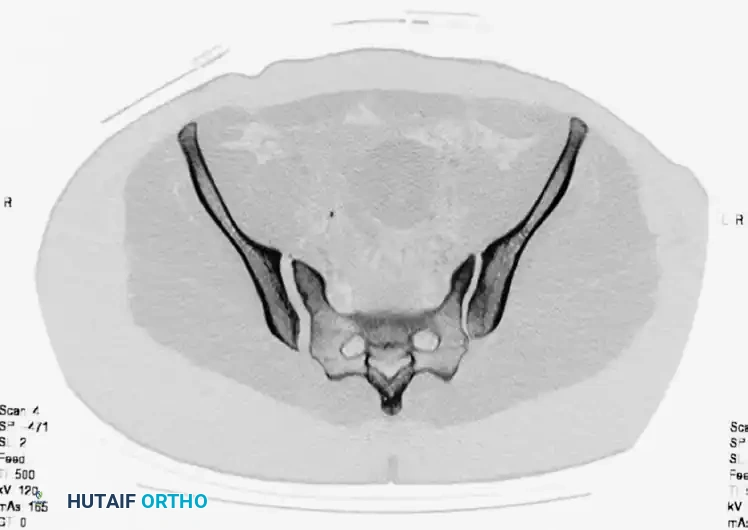

Axial CT imaging confirms the complete dissociation of the sacroiliac articulation, highlighting the profound instability of the posterior tension band.

FIGURE 56-45: Young and Burgess anteroposterior type III (AP III) pelvic ring injury with pubic diastasis and bilateral pubic rami fractures. A-C, Preoperative anteroposterior, inlet, and outlet views, respectively. D, Preoperative CT scan.